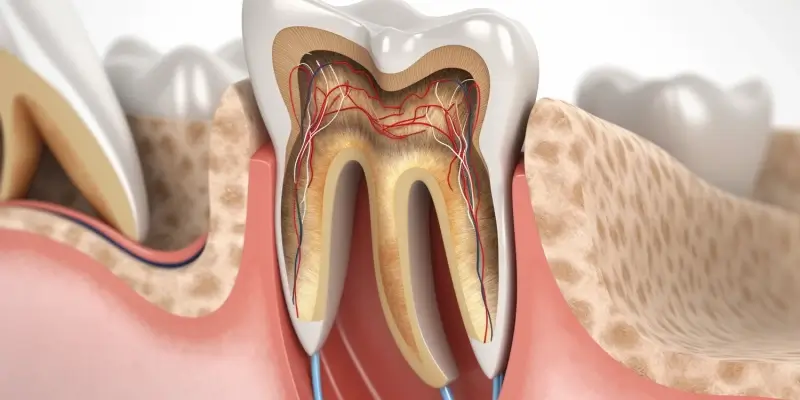

Piaskowanie zębów co to jest?

Piaskowanie zębów to nowoczesna metoda higieny jamy ustnej, która ma na celu usunięcie osadów, kamienia...

Piaskowanie ile trwa?

Piaskowanie to technika, która znajduje zastosowanie w wielu branżach, od budownictwa po renowację zabytków. Czas...

Czy z opryszczką można iść do dentysty?

Opryszczka to powszechna infekcja wirusowa, która może powodować wiele nieprzyjemnych objawów, takich jak ból, swędzenie...

Kiedy wypadają zęby mleczne?

Wypadanie zębów mlecznych to naturalny proces, który zazwyczaj zaczyna się w wieku około sześciu lat....

Kiedy wypadają mleczne zęby?

Wypadające mleczne zęby to naturalny proces, który zachodzi w życiu każdego dziecka. Zwykle zaczyna się...

Ile kosztują implanty górnej szczęki?

Implanty górnej szczęki to coraz popularniejsza metoda leczenia braków zębowych, a ich koszt w Polsce...

Czy implanty zębów bolą?

Implanty zębów to popularne rozwiązanie dla osób, które straciły zęby. Wiele osób zastanawia się, czy...

Implanty zębowe Lublin

Implanty zębowe w Lublinie to rozwiązanie, które zyskuje coraz większą popularność wśród osób borykających się...

Implanty zębów czy boli?

Implanty zębów to popularna metoda uzupełniania braków w uzębieniu, jednak wiele osób obawia się bólu...